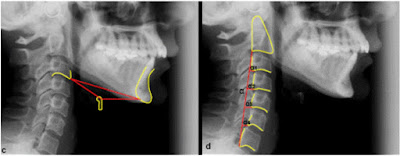

El hueso hioides se ubica en la zona anterior del cuello por debajo de la lengua y por encima del cartílago tiroides. En una teleradiografía lo encontramos por anterior a las vértebras C3 y C4. Así forma un enlace entre la cabeza y el cuello, sirviendo como punto de fijación a músculos y ligamentos que se insertan en la base del cráneo, mandíbula, escapula y mediastino superior. Está conectado con la columna cervical a través de las fascias cervicales.

Esta puede ser afectada por el espacio aéreo de la faringe, las funciones linguales, la posición de la columna cervical y la morfología craneofacial. Por ejemplo en sujetos de caras cortas se encuentra un hioides anteriorizado ocurriendo lo inverso en sujetos de caras largas.

La posición de la lengua, vías aéreas estrechas e importantes extensiones cráneo-cervicales pueden determinar una postura descendida del hioides. Un estrechamiento en el espacio faríngeo puede ser un factor predisponente para el síndrome de apnea obstructiva del sueño , lo que se ha observado en niños con este síndrome donde el hioides estaba posicionado más anterior e inferior de lo normal.

Chaves y cols. observaron que niños con asma y respiración bucal presentaban un ángulo cráneo vertebral de Rocabado reducido, teniendo como adaptación respiratoria la extensión de cabeza. Junto con este cambio angular observado del ángulo cráneo-vertebral, estos niños presentaron frecuentemente triángulos hioideos ausentes o invertidos.